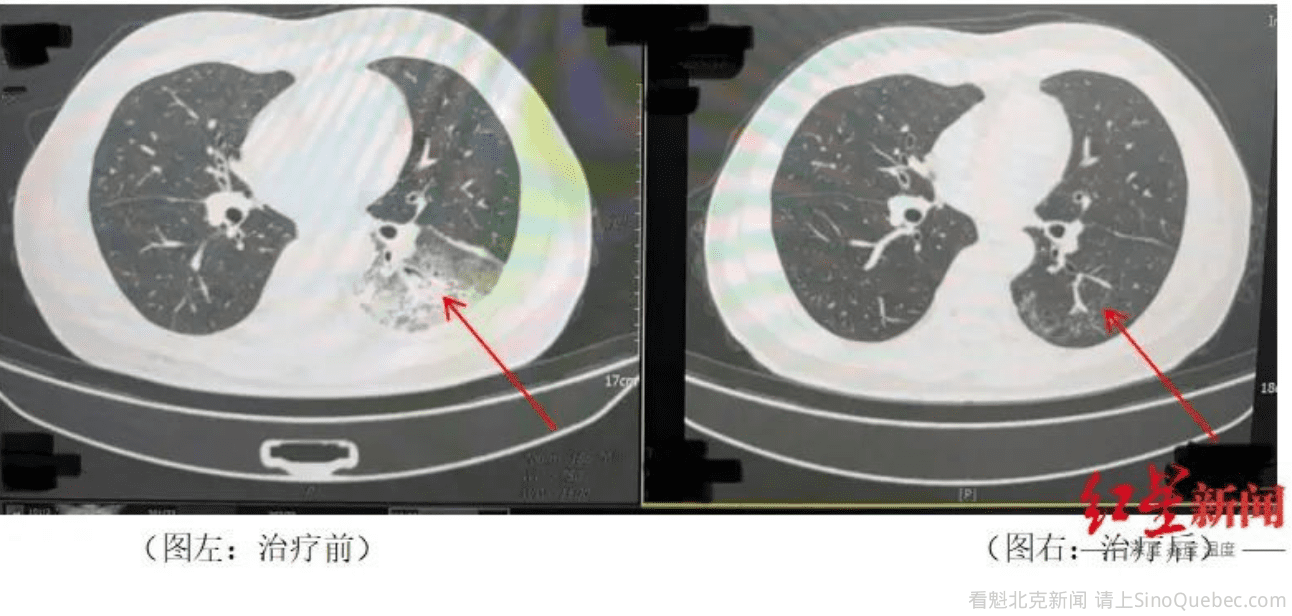

近日,成都气温逐步升高,市民李先生在开启尘封一年的空调后,竟意外患上了严重的军团菌肺炎,左肺接近“白”了一半。经过成都市第五人民医院感染性疾病科的诊断和治疗,李先生已康复出院。 据悉,开启空调降温3天后,李先生出现了肌肉酸痛、头痛、发热和咳嗽等症状。起初,他以为是吹空调吹感冒了,于是自行服用感冒药,但病情并未好转,反而愈发严重。家人见状,立即将他送往成都市第五人民医院感染性疾病科。胸部CT显示李先生的左肺已出现大面积白色影像,几乎占据一半肺部。经过肺泡灌洗NGS检测,最终确认“罪魁祸首”是嗜肺军团菌。 什么是军团菌肺炎?据成都市第五人民医院感染性疾病科主任许晓梅科普,军团菌是一种细菌,特别喜欢在水里和潮湿的环境中生长。嗜肺军团菌是其中一种,很容易让人得肺炎。这种肺炎很厉害,病情发展快,死亡率也比较高,尤其是免疫力差的人更容易中招。它主要是通过空调、热水器等设备排出的水雾传播,被人吸入后就会引发呼吸道感染。 据了解,李先生家的空调,已经有快一年没用过了,这次使用前也没有进行清洗,而清洁与通风是预防的关键。 许晓梅介绍,感染军团菌后,通常会在2到10天内出现症状,比如发冷、发烧、干咳、呼吸困难,还可能伴有头痛、肌肉酸痛、恶心、呕吐,甚至意识模糊等。如果出现这些症状,吃感冒药或普通抗生素(如青霉素、头孢)没效果,一定要警惕军团菌肺炎,及时就医。 目前没有预防军团菌肺炎的疫苗,但做好以下几点可以有效降低感染风险:定期清洗空调、热水器和淋浴喷头,避免细菌滋生;保持室内通风,不要长时间紧闭门窗;使用空调时,注意清洁和维护。 |